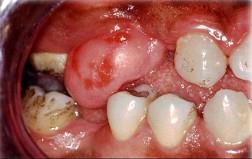

组图为口内纤维瘤的外观,关于此病的描述不正确的是()A.主要由纤维组织构成B.生长一般较缓慢C.肿瘤边界清楚D.手术后不易复发...

问题 组图为口内纤维瘤的外观,关于此病的描述不正确的是()

选项 A.主要由纤维组织构成 B.生长一般较缓慢 C.肿瘤边界清楚 D.手术后不易复发 E.有可能恶变

答案 D